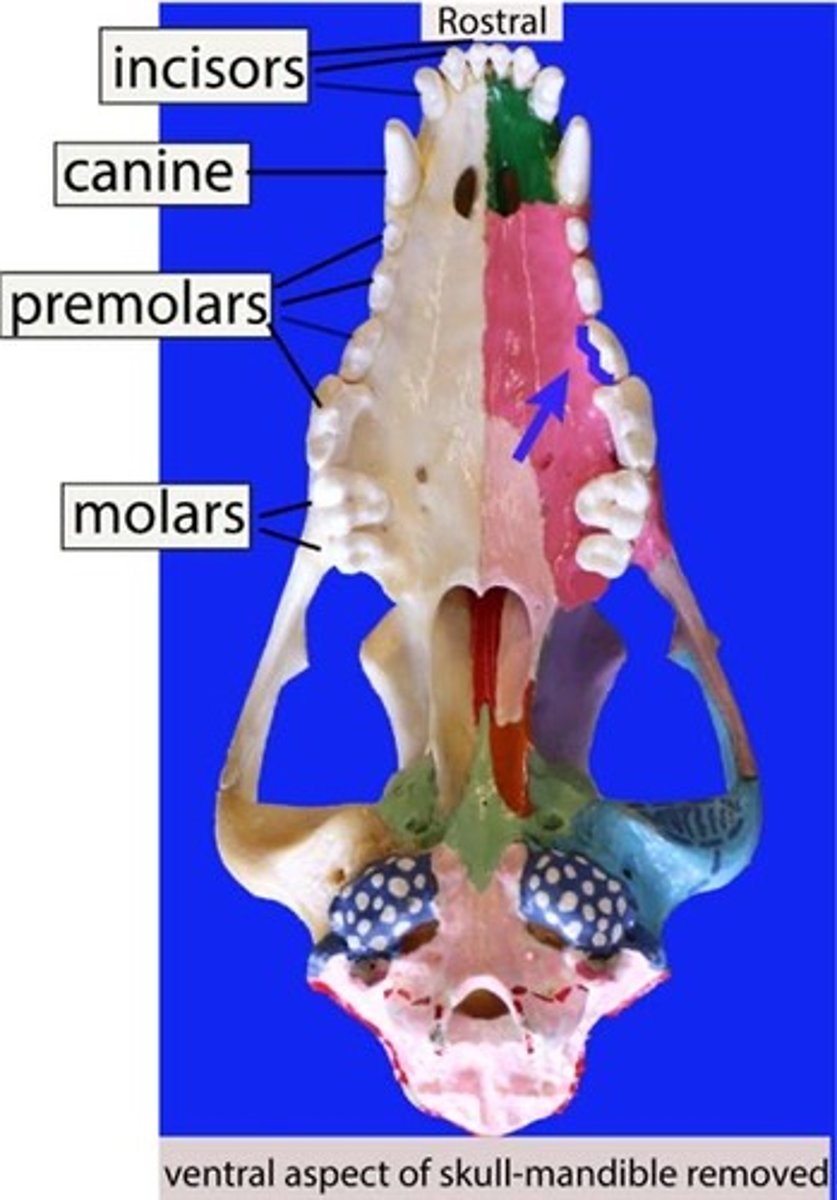

incisor

Identify the general type of tooth the arrow is pointing to

canine

Identify the general type of tooth the arrow is pointing to

premolar

Identify the general type of tooth the arrow is pointing to

molar

Identify the general type of tooth the arrow is pointing to

incisors

What type of teeth are found in the incisive bone

canines, premolars, molars

What type of teeth are found in the maxillary bone?

incisors

Identify the type of teeth shaded.

premolars

Identify the type of teeth shaded.

Canines

Identify the type of teeth shaded.

Molars

Identify the type of teeth shaded